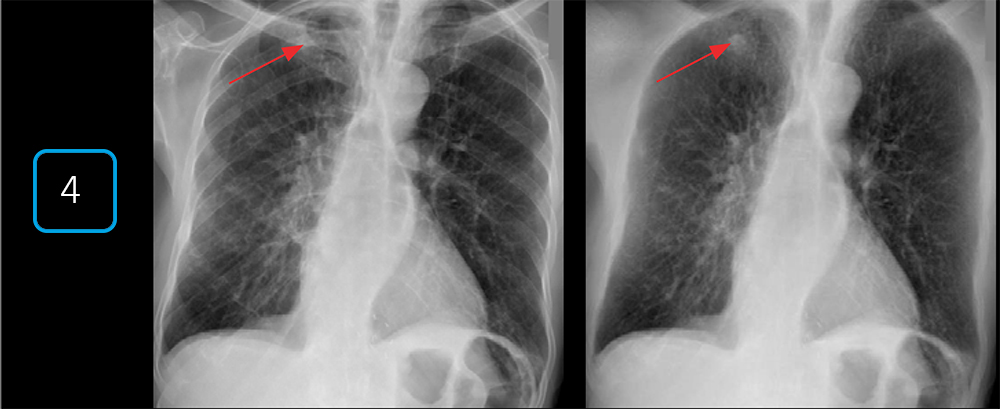

- Подавление костной ткани (Bone Suppression)

Специальный алгоритм искусственно удаляет изображение костей с готового снимка грудной клетки. Это помогает лучше визуализировать затемнения в легких, которые могли быть скрыты за рёбрами, выступая дополнительным инструментом анализа без повторного облучения.